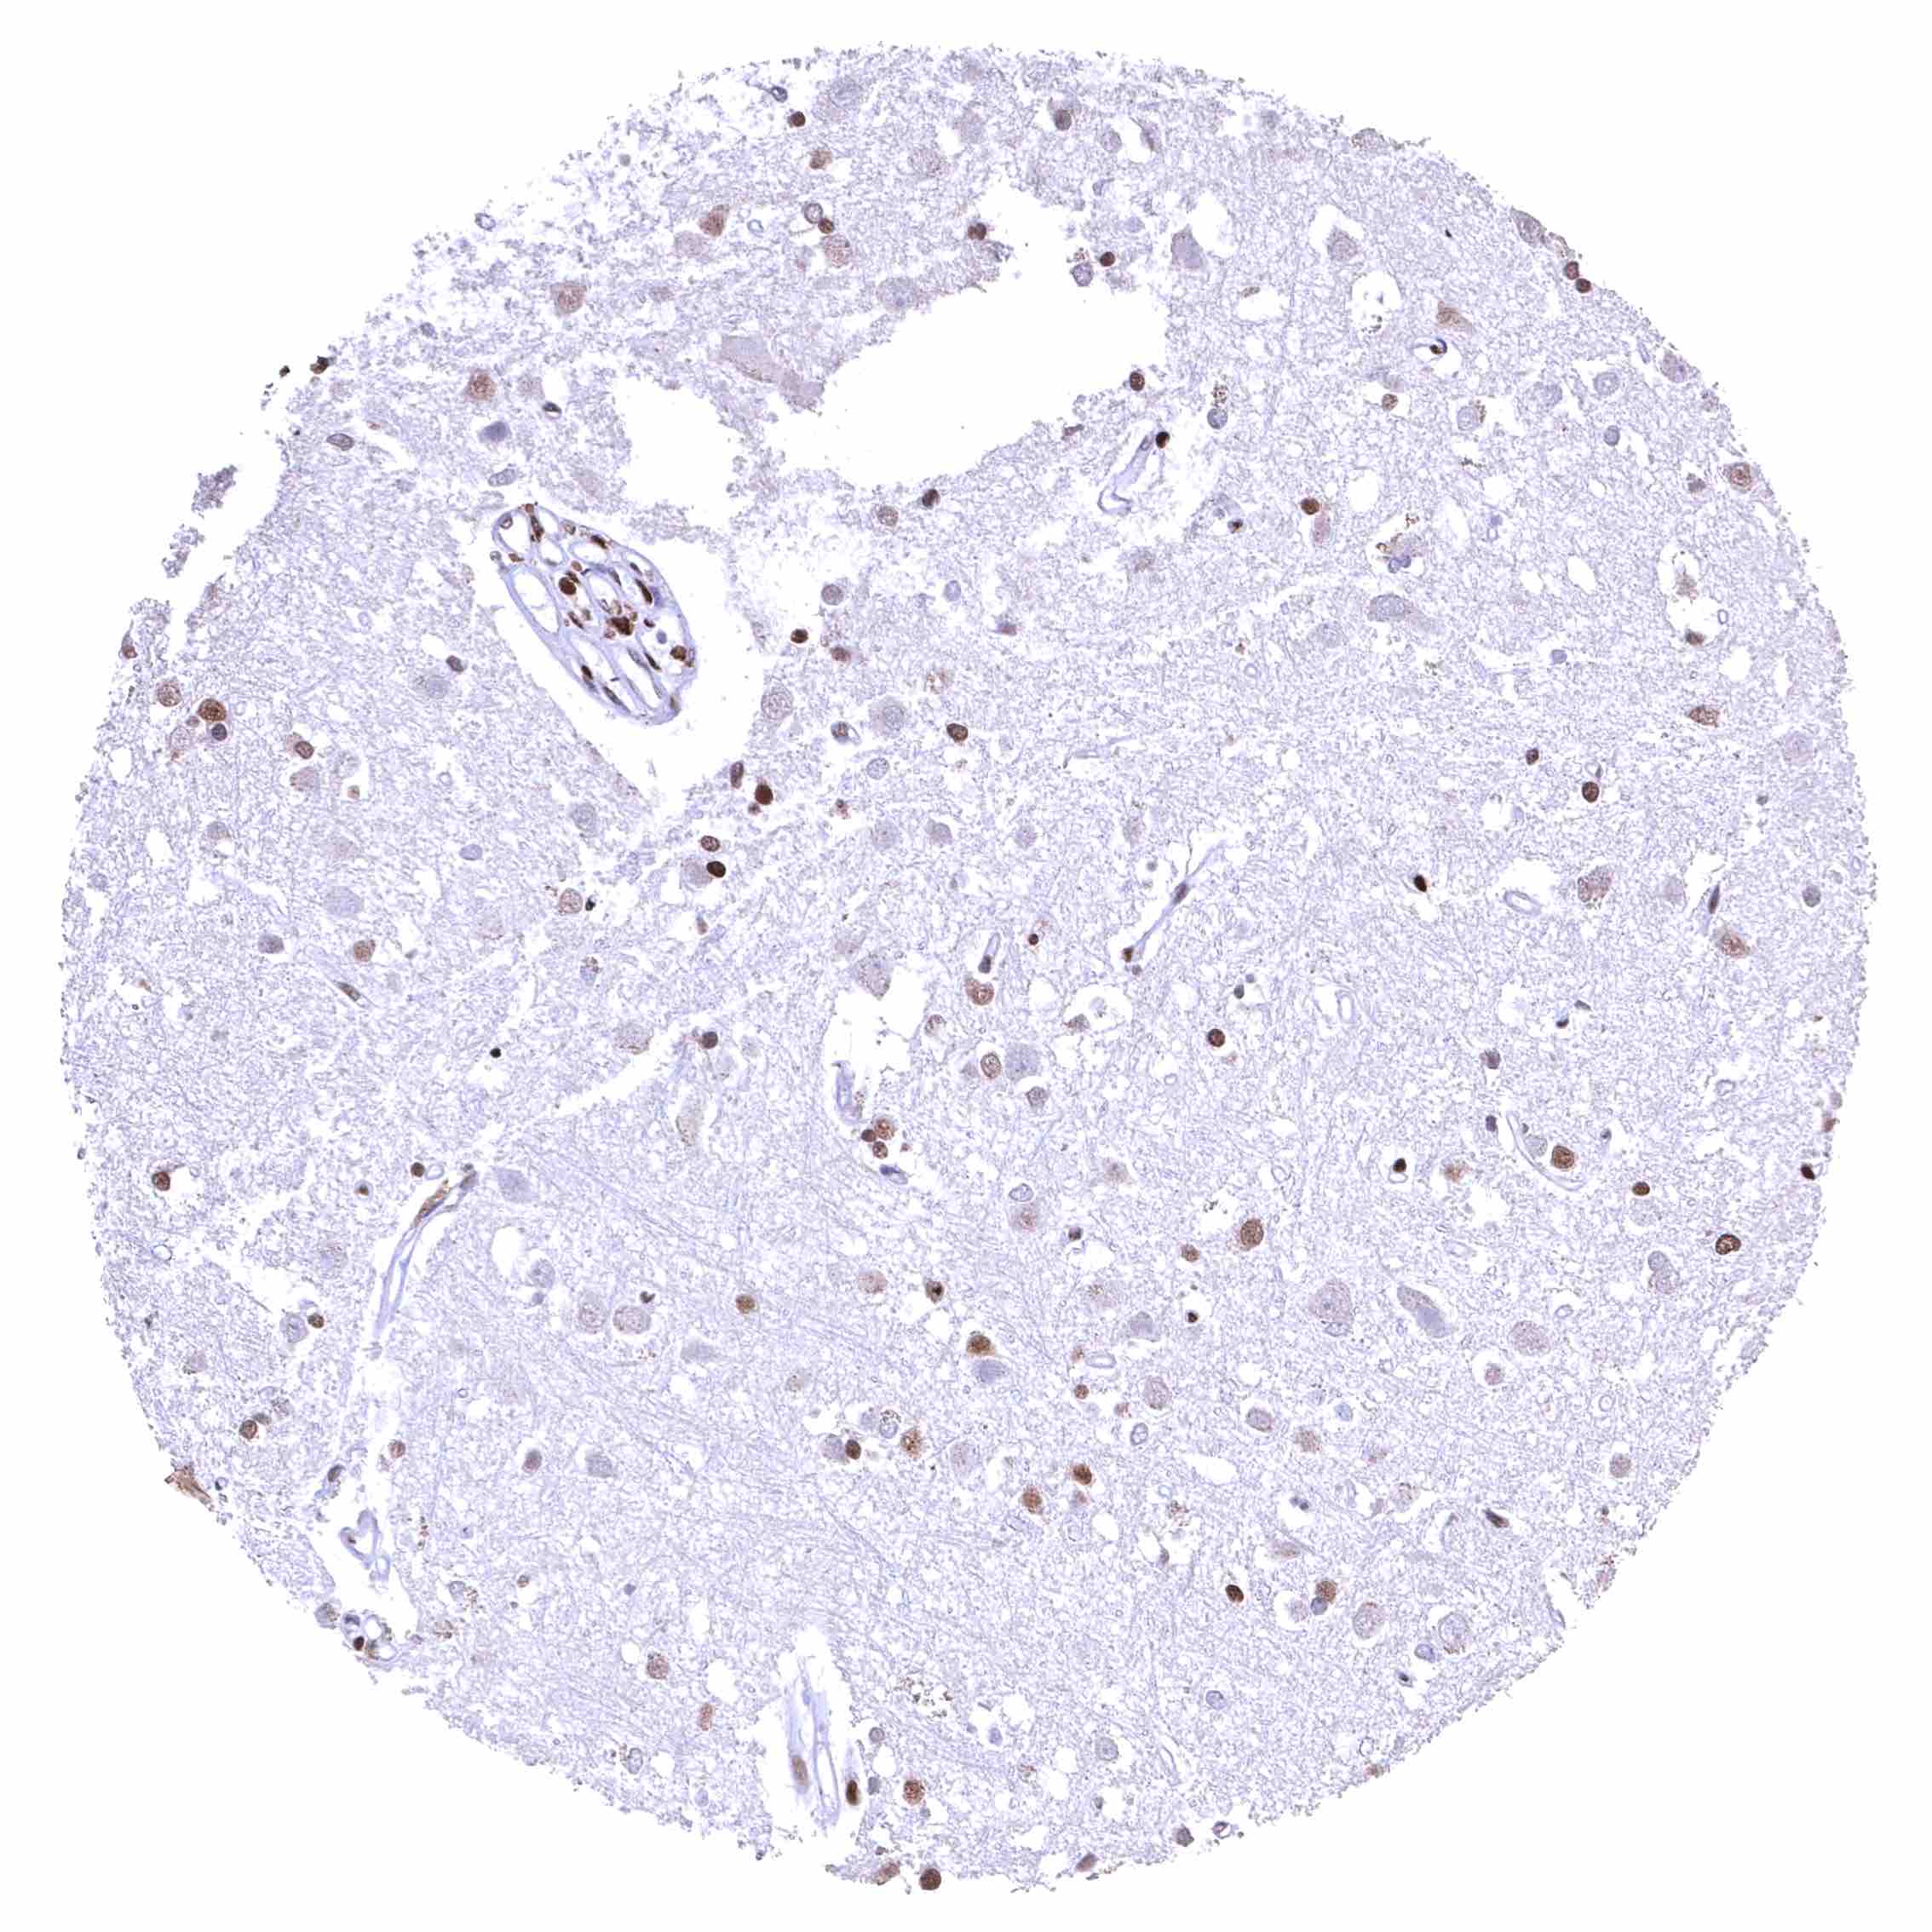

Cerebrum, grey matter – BRD4 staining is strong in glia cells but low or absent in neuronal cells.